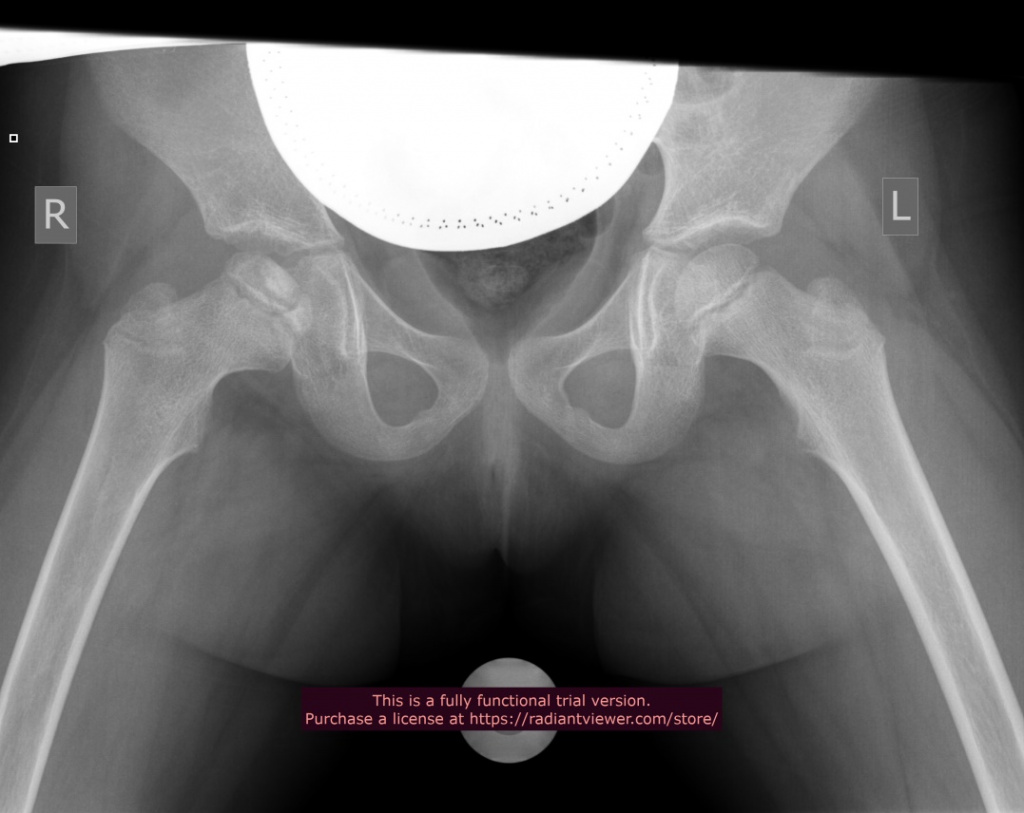

2013 год Пациентка Т., 5 лет |